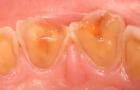

酸蝕症はこのように歯が溶け出して、悲惨なことになりますよ。

早めに来院しましょう。

みかんはかなり歯がしみますよね。

みかんをいつも1日に2個以上食べる人は胃液による酸蝕と同じくらいに歯が溶けますよ。みかんを毎日食べるのはやめましょう。